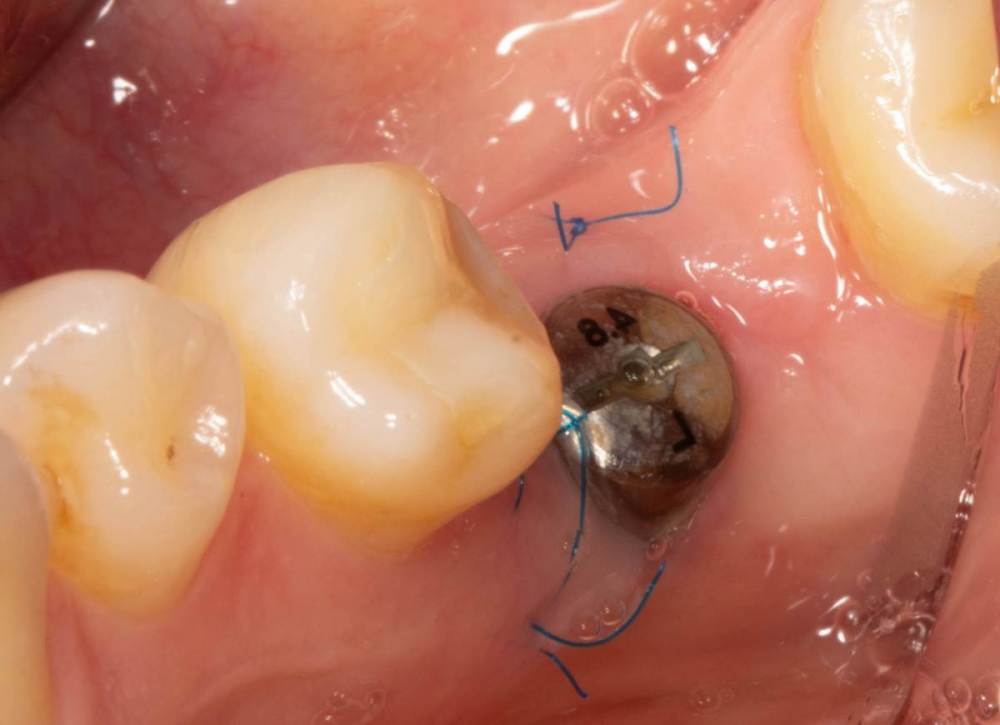

Женька Опубликовано 3 июля, 2023 Автор Поделиться Опубликовано 3 июля, 2023 Возвращаясь к теме) Не фартануло... думаю "ручку" чемодана надо было делать полноценно с захватом сосочков. И перемещать целиком. Через 7 дней ни трансплантата, ни швов, ни объёма( Админ, не получается изображение развернуть и нормально вставить, как я не крутил. Ссылка на комментарий